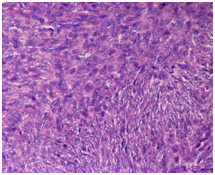

A 48-year-old male presented with swelling on the left breast. On examination, there was a nodular swelling about 13x10x5cm in size. It was non-tender and freely mobile over the pectoralis muscle. There was no discharge from nipple and no palpable axillary nodes. The fine needle aspiration cytology (FNAC) report was inconclusive. All the routine blood parameters and chest X-ray were normal. A wide local excision was done. Grossly, specimen consists of grey white nodular tissue bit measuring 13x10x5cm (Figure 1). Histopathologically, the slide showed storiform arrangement of tumour cells with uniform population of fusiform or spindle shaped cells with little variation in shape and size with scant cytoplasm (Figure 2) (Figure 3). Immunohistochemistry was done which showed positivity for CD34 (Figure 4).

Histopathology reveals relatively uniform densely grouped fusiform cells, with elongated nuclei without significant cytologic atypia or pleomorphism in characteristic storiform arrangement.16 Immunohistochemical findings are positivity to CD34 in 84–100% and to vimentin and negativity to other markers such as S-100, HMB45, desmin and actin.1,3,17,18 CD34 positivity is seen in different variants of soft tissue tumour. However, morphological pattern followed by immunohistochemical marker plays a significant role in differentiating DFSP from other tumours with CD4 positivity.